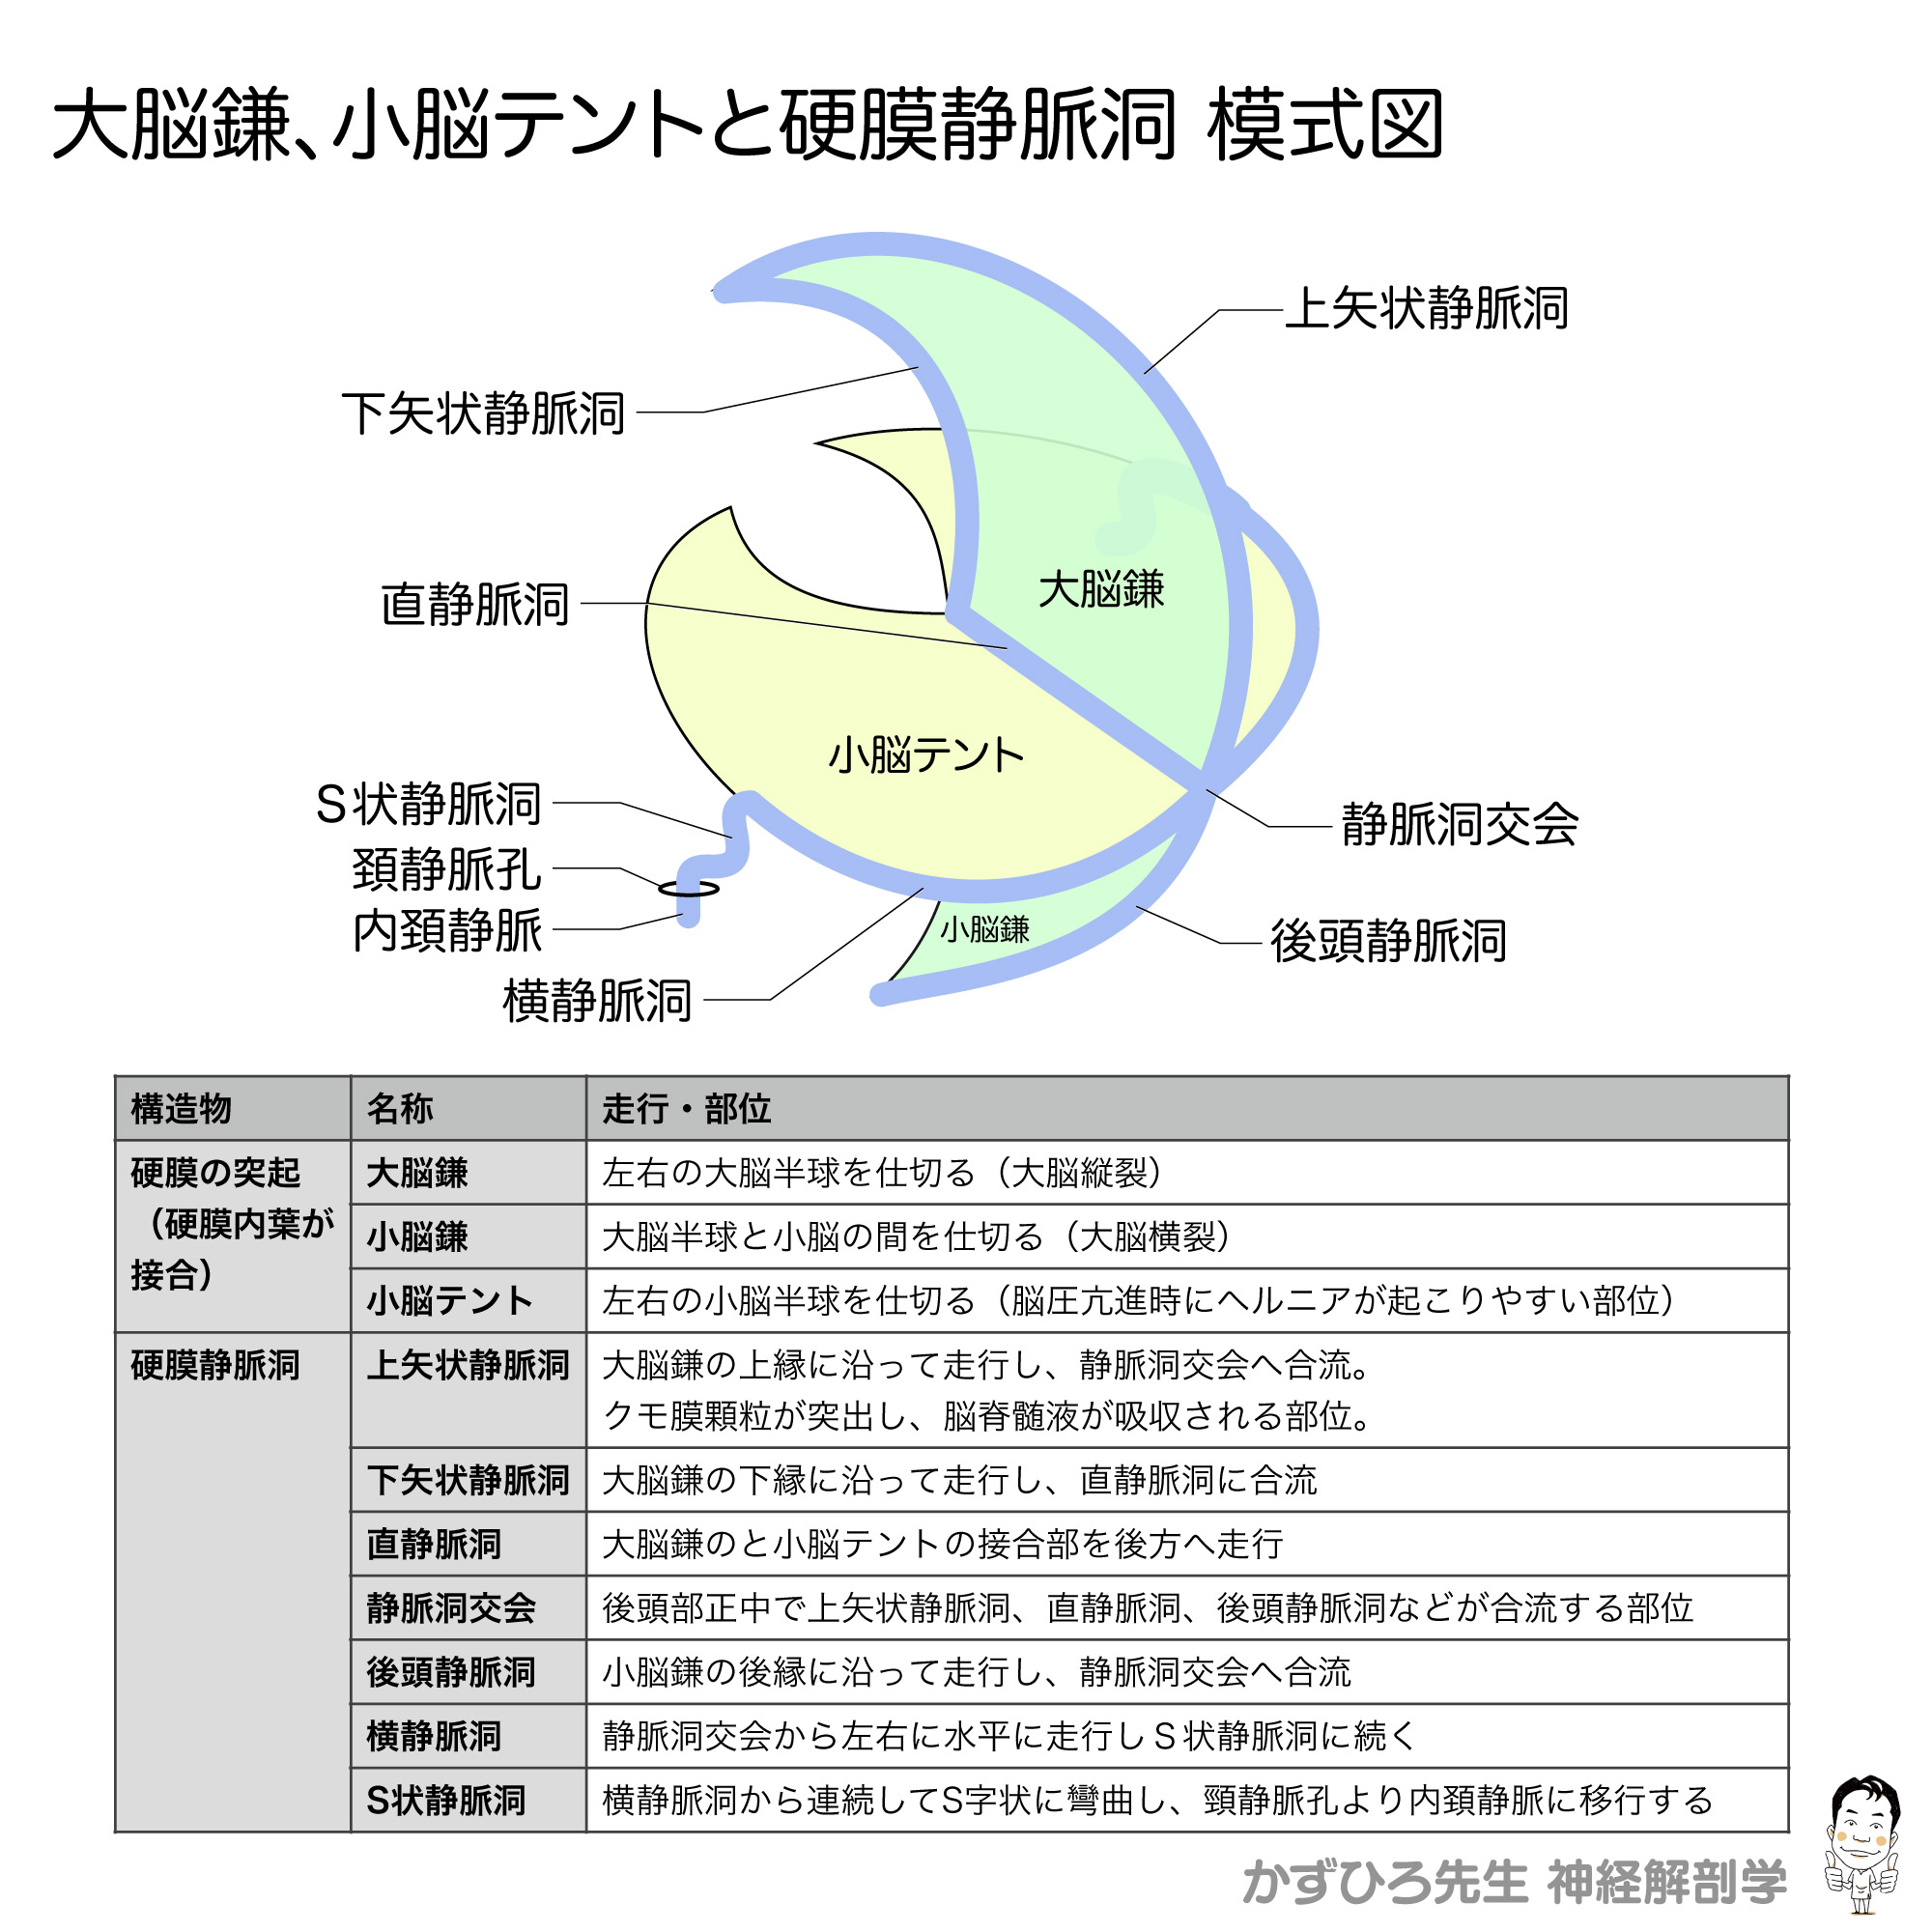

裁断済】マイヤース腹部放射線診断学 発生学的・解剖学的アプローチ。マイヤース腹部放射線診断学: 発生学的・解剖学的アプローチ。マイヤース腹部放射線診断学 発生学的・解剖学的アプローチ。mochi*°様✳︎ 小さなスコーンとポルポロン * スコーン 2月*。「マイヤース腹部放射線診断学 発生学的・解剖学的アプローチ」太田 光泰定価: ¥ 15400円+税即購入OKです(^^)・裁断済みです。書き込みはなく綺麗な状態です。裁断してある中古品であること、素人による裁断であることをご理解のうえ、ご購入下さい。神経質な方は購入をお控えください。・1-2日で発送致しますが、週末や連休中は発送が休み明けになることがあるかも知れません。。徹底的解剖学 | 黒澤一弘(かずひろ先生)による解剖生理学講座。綴じ口より裁断されておりバラバラの状態です。vol2 岩越真一先生(放射線医学 助教) | 奈良県立医科大学。グレイ解剖学 原著第5版 / Anatomy 今日も明日も/グレイ解剖学。裁断しているため、「傷や汚れあり」 にました。福井大学における革新的な画像医学教育への挑戦─ITとAiをベース。ポータブル電磁超音波探傷器 VOLTA2 (Innerspec Technologies。・ほとんど使用しておりませんが、多少のキズや小さな角折れ等あるかもしれません。黒澤一弘(かずひろ)解剖学IT教育・指圧師・ラダック on X。JRC2012 ziosoft/AMIN Seminar Report 超四次元画像。・梱包は丁寧に行うようにしておりますが、配送中の破損は保証できませんので、ご了承下さい。徹底的解剖学 | 黒澤一弘(かずひろ先生)による解剖生理学講座。画像診断を学ぼう 単純X線からCT・MRI・超音波まで 第2版。その際はご容赦下さい。【裁断済】小児・成育循環器学 改訂第2版